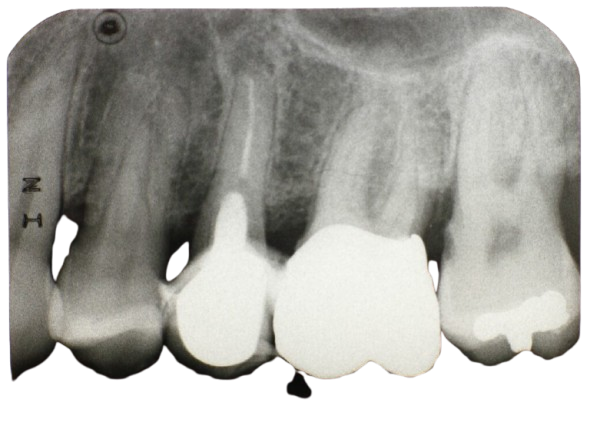

Dentalne pojedinačne RTG snimke (intraoralne rendgenske snimke) služe za precizan prikaz jednog ili više zuba te okolnih struktura – kosti, korijena i parodontalnog prostora. To su osnovne dijagnostičke snimke koje stomatolozi koriste za otkrivanje karijesa, upala, oštećenja kosti ili procjenu uspješnosti liječenja zuba.

Bite-wing snimka – koristi se za prikaz međuzubnih prostora i otkrivanje karijesa između zuba.